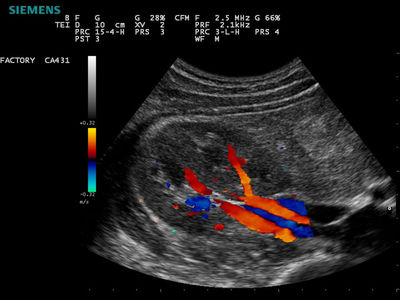

Question 12

Question

Is it true that colour Dopplers show the difference between arteries and veins?

Answer

• True

• False